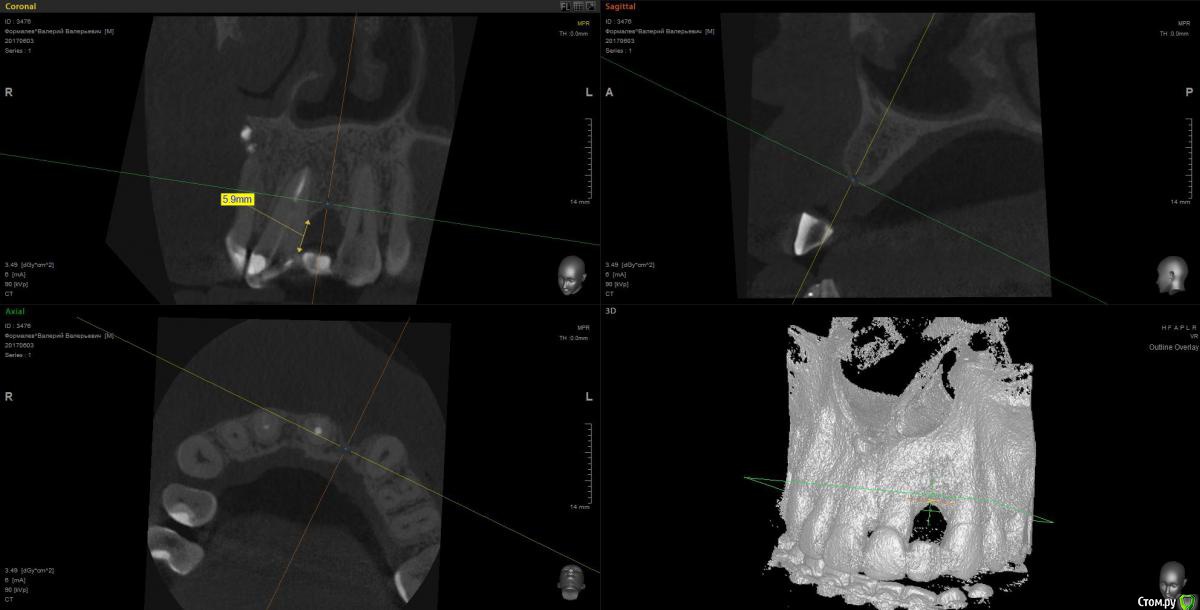

Kostoprav Опубликовано 12 июня, 2017 Поделиться Опубликовано 12 июня, 2017 Уважаемые коллеги! подскажите советом что бы вы сделали в данной ситуации.резорбция кости на корне 21 зуба по высоте почти 6 мм, пациент хочет имплант.боюсь если просто закрутить винт + сст эстетики не будет ни какой так как нет костной поддержки мягких тканей Ссылка на комментарий

Kostoprav Опубликовано 12 июня, 2017 Автор Поделиться Опубликовано 12 июня, 2017 Ситуация во рту Ссылка на комментарий